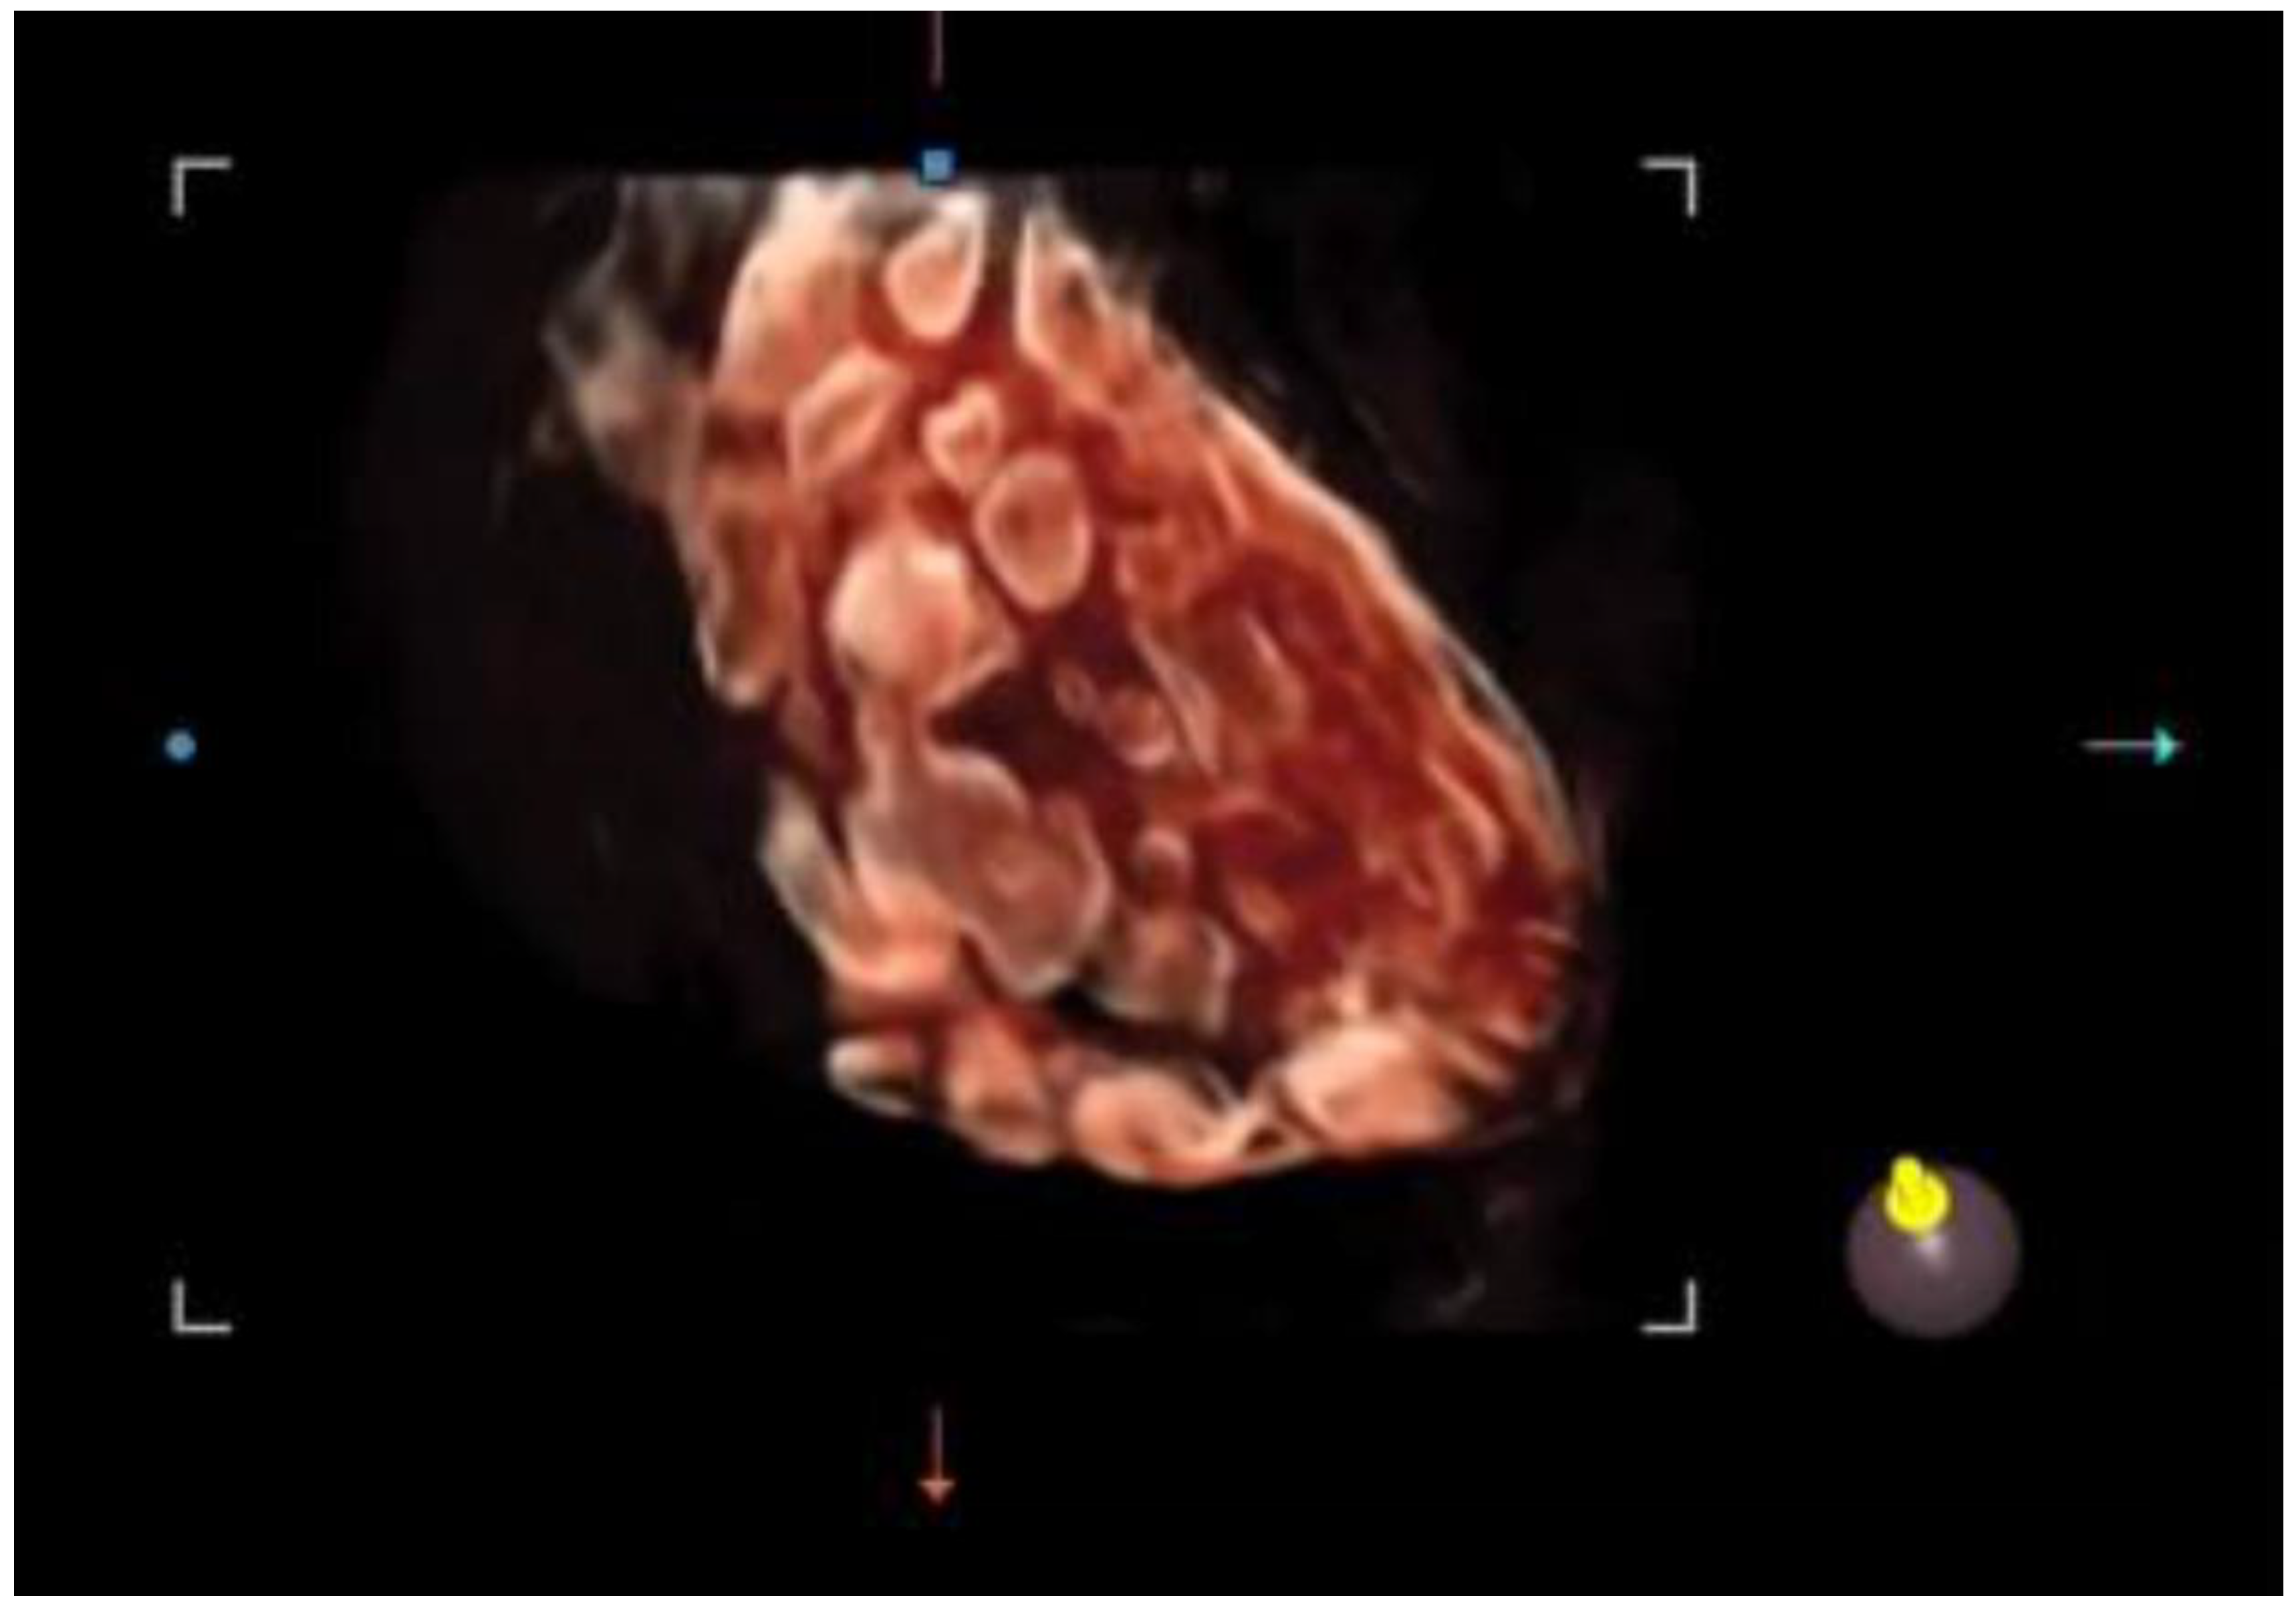

Recently, 3D ultrasound has gained increasing popularity in studying PCOS and reproductive medicine. It appears to provide a more reliable and objective assessment of ovarian volume and morphology, stromal area, follicle count, and overall blood flow than traditional 2D methods, as shown in Figure 2.

Figure 2.

A 3D study of the ovary: identification and measurements of the ovarian follicles to rapidly assess the size, follicular status, and spatial arrangement.

It offers a noninvasive, safe, and painless option for evaluating the internal genitalia in young women. Moreover, 3D ultrasounds can detect more follicles than 2D imaging, enhancing diagnostic accuracy [46,47]. In adolescents, where the diagnosis of PCOS remains uncertain after clinical and laboratory evaluation, magnetic resonance imaging (MRI) could be considered an alternative imaging modality. However, if 3D-TA approaches become widely available, with suitably high-resolution probes, 3D ultrasound may reduce the reliance on MRI in borderline cases [48]. Among the recently employed three-dimensional ultrasound techniques in evaluating the PCOM, inversion mode provides a highly effective way to highlight fluid-filled structures such as antral follicles. By virtually inverting the echogenic signals, the typically hypoechoic areas (e.g., follicular fluid) appear hyperechoic, allowing for easier follicle detection and quantification (Figure 3). This method can reduce the error in follicle counting, enhance the visualization of the follicular layout, and provide additional insights into the stromal–follicular relationship [49].

Figure 3.

Three-dimensional ultrasound scan using the inversion mode.